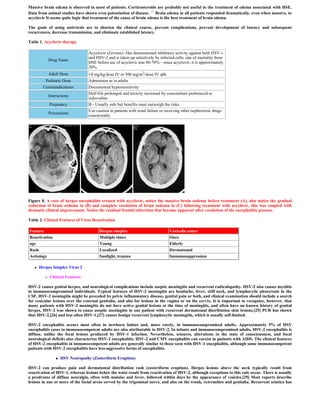

Figure 1. (A,B,C) A case of herpes encephalitis, precontrast CT scan. Notice the bitemporal, hypodensity, more in the left side. Also notice

insular, cingulate, and posterior orbital frontal hypodensities, more on the left side. A haemorrhagic component is noticed at the left temporal

lobe. The CT hypodensity represent vasogenic edema secondary to the associated vasculopathy.

Figure 2. (A,B,C) Herpes encephalitis, precontrast CT scan. Notice the insular, cingulate, and posterior orbital frontal hypodensities, more on

the left side. The CT hypodensity represent vasogenic edema secondary to the associated vasculopathy. Mild mass effect is noticed on the left

side.